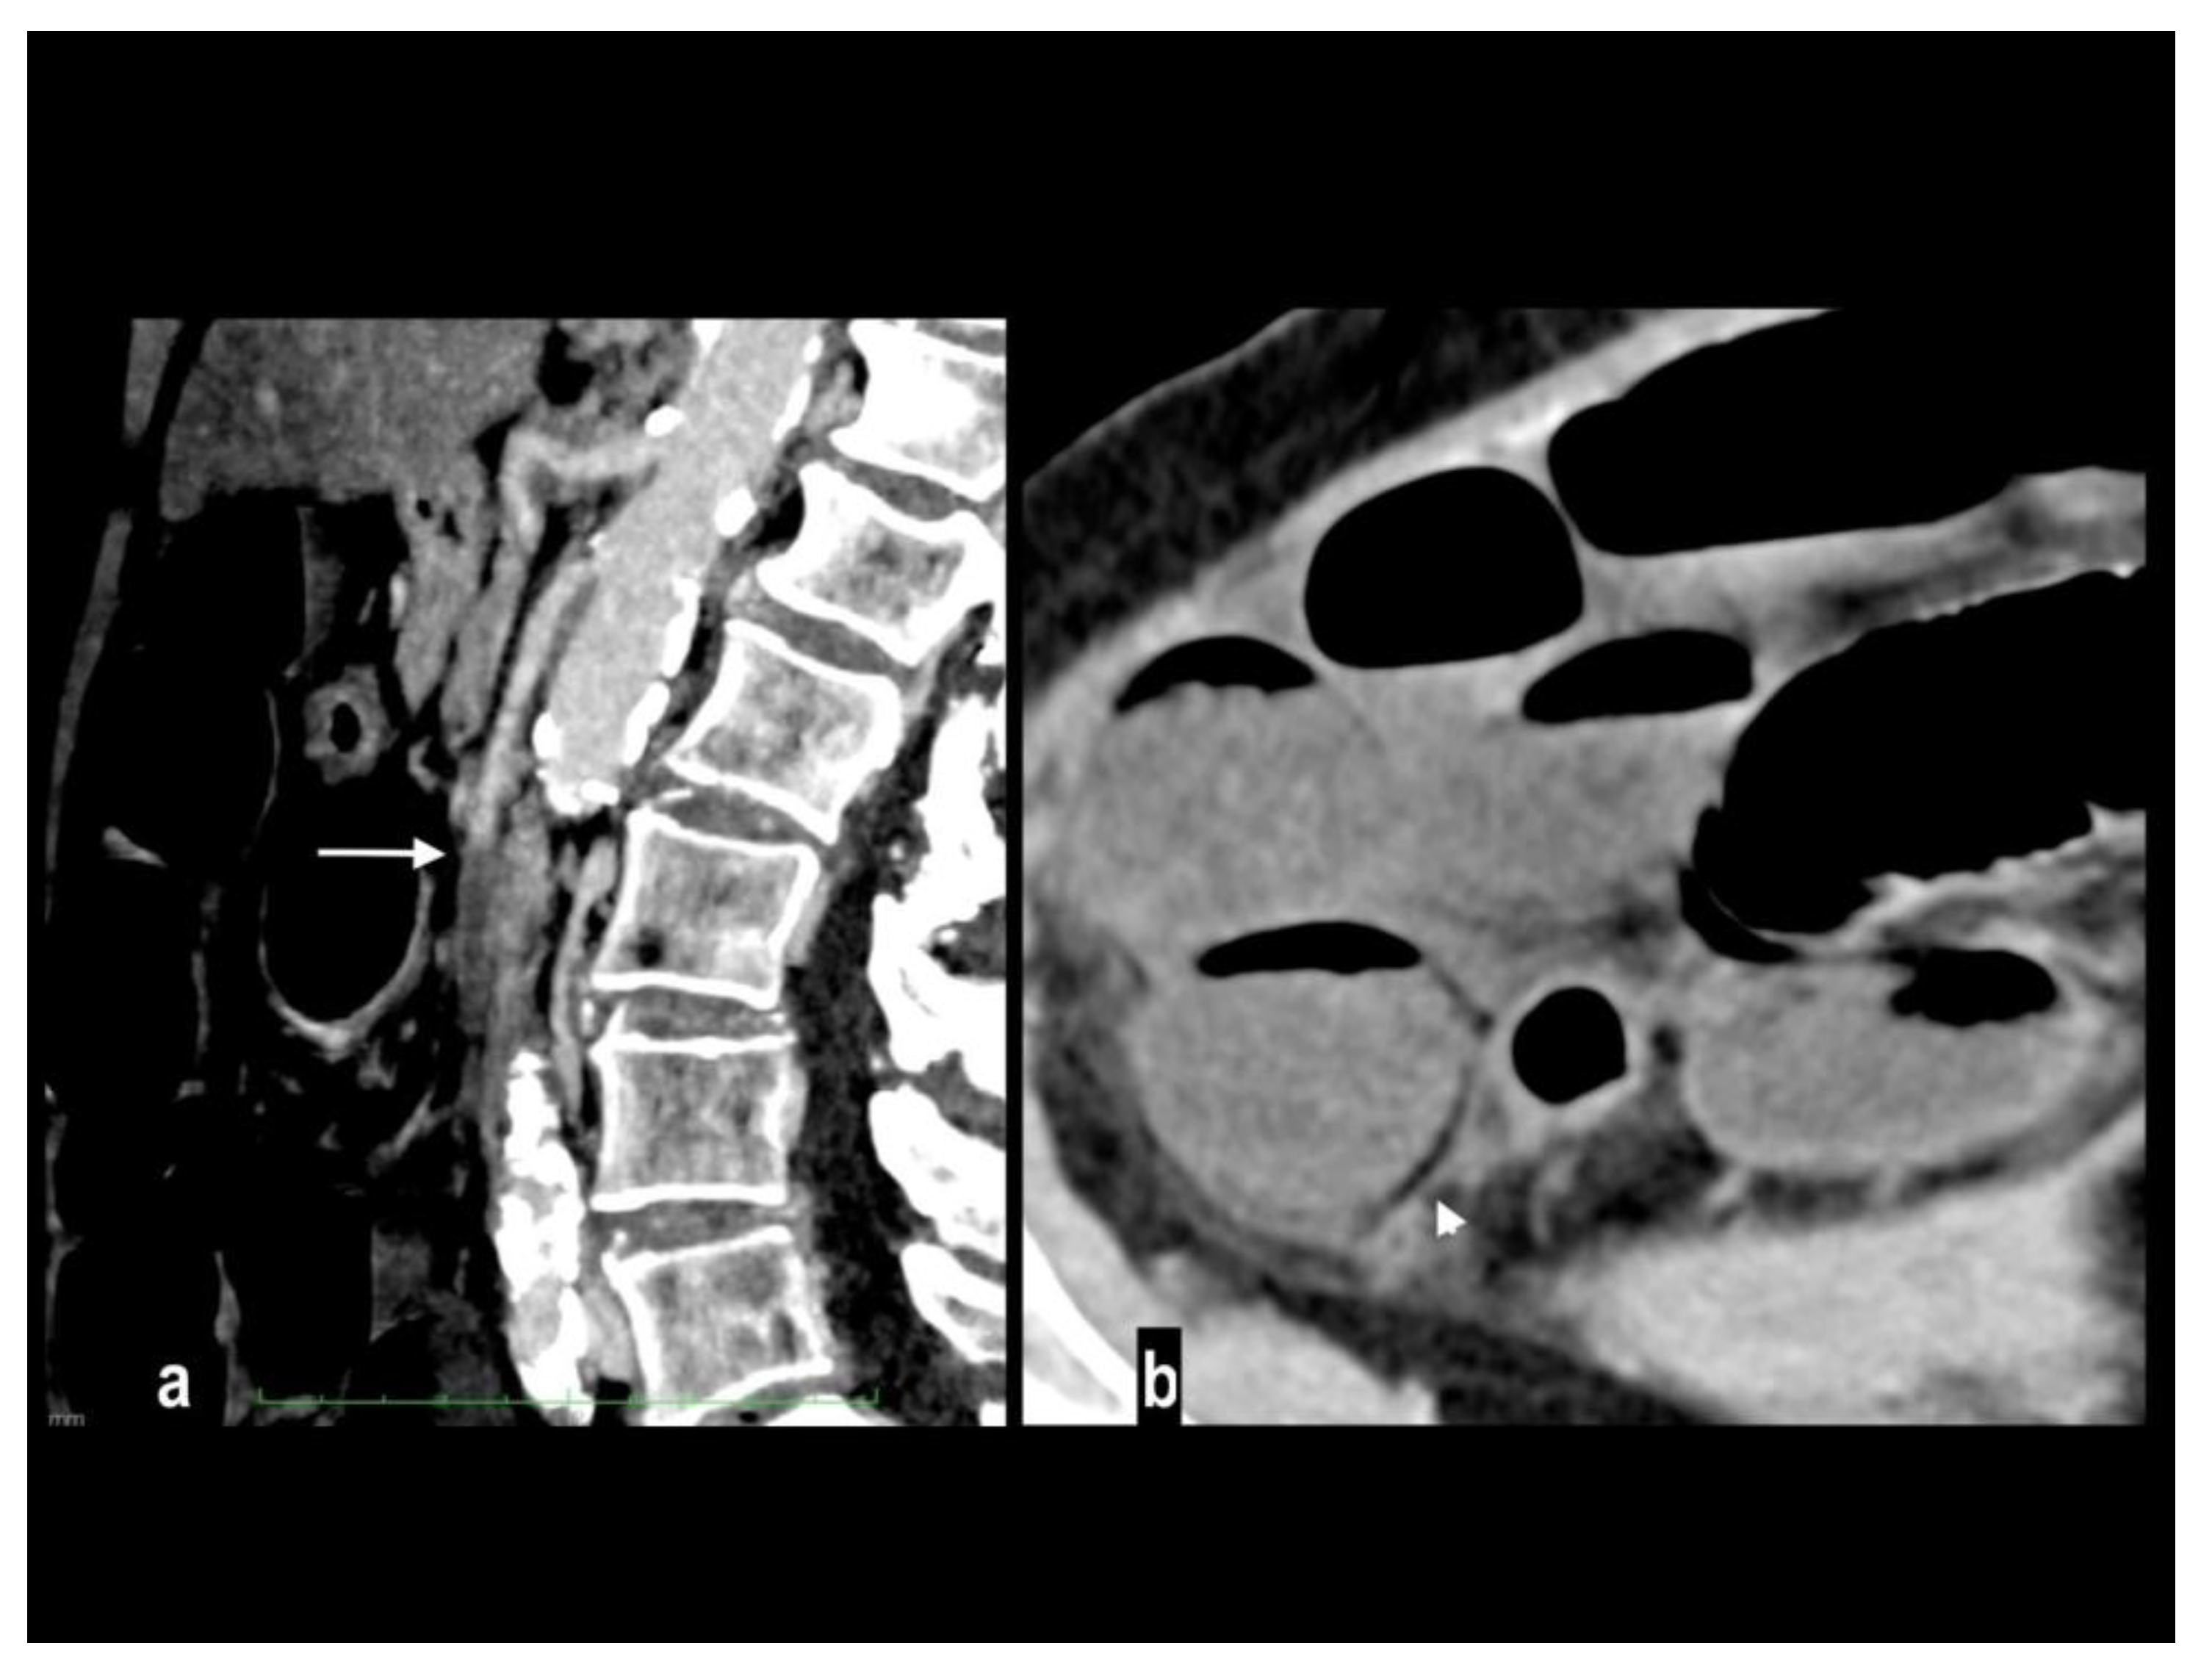

Figure 9. A 86-year-old patient presenting at the emergency department in coma. Blood lactate value was 14 mmol/l. An abdominal portal-phase scan showed SMA embolic occlusion (figure 9a, arrow) and diffuse dilation of small bowel loops with segmentary parietal pneumatosis (figure 9b, arrowhead). Multiple necrotic small bowel loops were found at surgery. The patient died the day after.